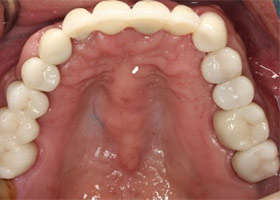

經由多顆人工植牙及全瓷假牙的全口重建,牙周病治療讓病人恢復咬合的功能與美觀,也易於每日的清潔保養。

治療後

proimages/Case/dentalimplant/10/02/after02.jpg